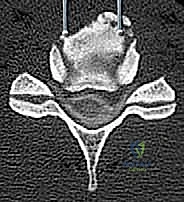

- التصوير المقطعي المحوسب (CT Scan): ضروري جداً لتقييم البنية العظمية، التكلسات (مثل OPLL)، والكسور بدقة ثلاثية الأبعاد.

الخطوة 3: استئصال الأقراص الغضروفية وجسم الفقرة (Corpectomy)

باستخدام الميكروسكوب الجراحي وأدوات دقيقة جداً، يتم أولاً إزالة الأقراص الغضروفية أعلى وأسفل الفقرة المستهدفة. بعد ذلك، يتم استئصال جسم الفقرة العظمي المتضرر بعناية فائقة لفتح مساحة واسعة وتحرير الحبل الشوكي المضغوط.